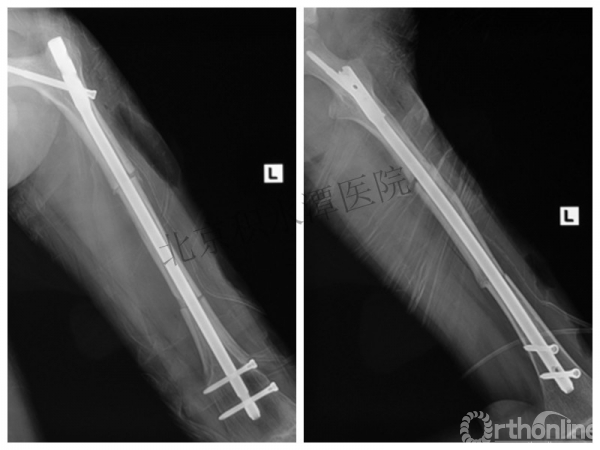

男孩、9岁,滑雪受伤,胫腓骨螺旋形骨折(粉碎性)

手法整复,石膏制动!

整复后7天

儿童具备强大的愈合潜力,同样也有极强的塑形能力